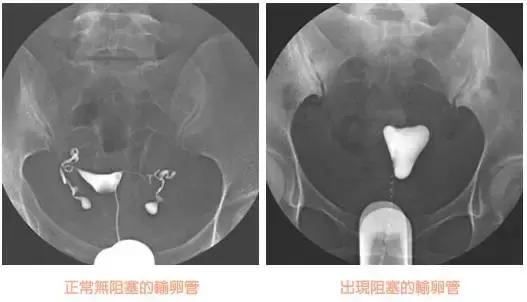

问题五:怎么看造影片?

怎么看懂造影片,啥也不说,上图